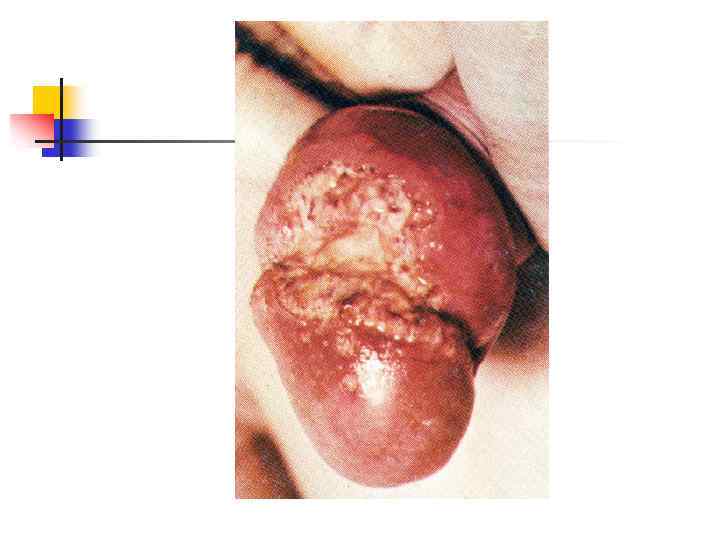

Герпес половых органов: первичная инфекция Множественные эрозии на вульве и коже промежности. Эрозии чрезвычайно болезненны, многие из них сливаются между собой. Увеличены паховые лимфоузлы, мочеиспускание причиняет жгучую боль

Герпес половых органов: первичная инфекция Множественные эрозии на вульве и коже промежности. Эрозии чрезвычайно болезненны, многие из них сливаются между собой. Увеличены паховые лимфоузлы, мочеиспускание причиняет жгучую боль